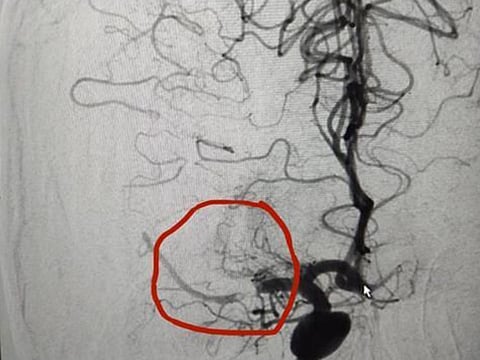

He added: “The scan showed that there was decreased blood supply to the right side of her brain. We had to take a quick decision to make - to either use a blood thinner, which could risk the life of the baby or do an intervention using a thrombectomy catheter. We decided on the latter, in this case we used just the lowest doses of radiation to get a less clear contrast picture so as to minimise any damage to the foetus.

“We also decided to do the procedure under local anaesthesia. The interventional procedure clearly showed that a major artery was affected and the right side of her brain was completely occluded. In case of strokes, brain as cells die every second.”

Dr Al Sibaie continued: “The challenge was to go in quickly, use the special catheter and use suction to extract the clot. She came to the emergency at 4.35pm and we were able to operate on her by 5.33pm, within one hour of her arrival, within the first hour of the stroke episode. The quick intervention helped as the patient showed immediate symptoms of recovery as soon as the clot was removed and blood supply was restored to that section. Later, a gynaecologist examined the patient and was able to confirm the foetus was doing well. The family was very happy as the patient recovered very quickly and within two days was able to go home.”